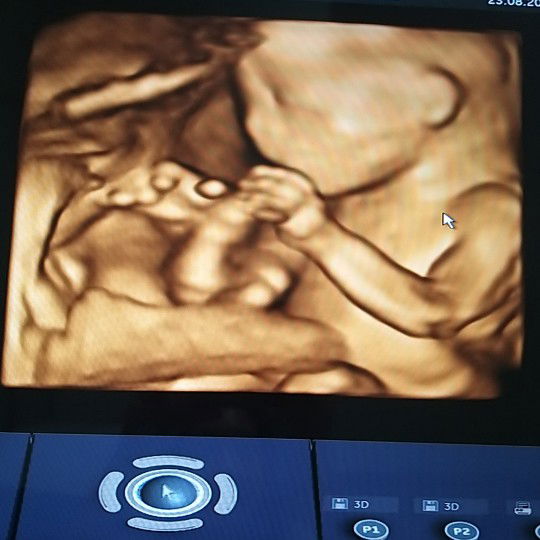

แชร์ประสบการณ์ ผ่าไส้ติ่งตอนท้อง 30 สัปดาห์

มีอาการช่วงแรกแค่ปวดท้อง อึดอัด แน่นทัอง ในช่วงค่ำ คิดว่าคงแค่ทานอาหารมากไป แต่ทั้งคืนนอนไม่ค่อยหลับเลย จนเที่ยงคืนกว่าอาเจียนพุ่งไปครั้งนึง อาการอึดอัดดีขึ้น แต่ยังคงปวดมากอยู่ คิดว่าคงจะอาหารเป็นพิษ ตอนเช้าเลยไปหาหมอซะหน่อย พอพบหมอตรวจร่างกาย หมอสงสัยไส้ติ่งอักเสบ รีบเก็บปัสสาวะ เก็บเลือดไปตรวจ สั่ง u/s ปรึกษาหมอ 3 แผนก ดูผลตรวจและตรวจร่างกายอย่างละเอียดจนยืนยันว่าใช่ไส้ติ่งอักเสบแน่ๆแล้ว เตรียมผ่าได้เลย หมออธิบายว่าการผ่าตัดในคนท้องอายุครรภ์เยอะแบบนี้ ไม่สามารถส่องกล้องผ่าได้ ต้องผ่าเปิด เพราะตำแหน่งไส้มันคลาดเคลื่อนไปเยอะมากแต่ไม่ต้องกังวลมันยาก แต่มันทำได้ เราก็เชื่อใจหมอเต็มที่ จนการผ่าตัดผ่านไปเรียบร้อย ลูกก็ยังคงดิ้นเยอะ แม่ก็เจ็บแผลมากหน่อย ดีที่วินิจฉัยได้เร็วเพราะถ้าไส้ติ่งแตก เรื่องคงยุ่งยากกว่านี้มาก